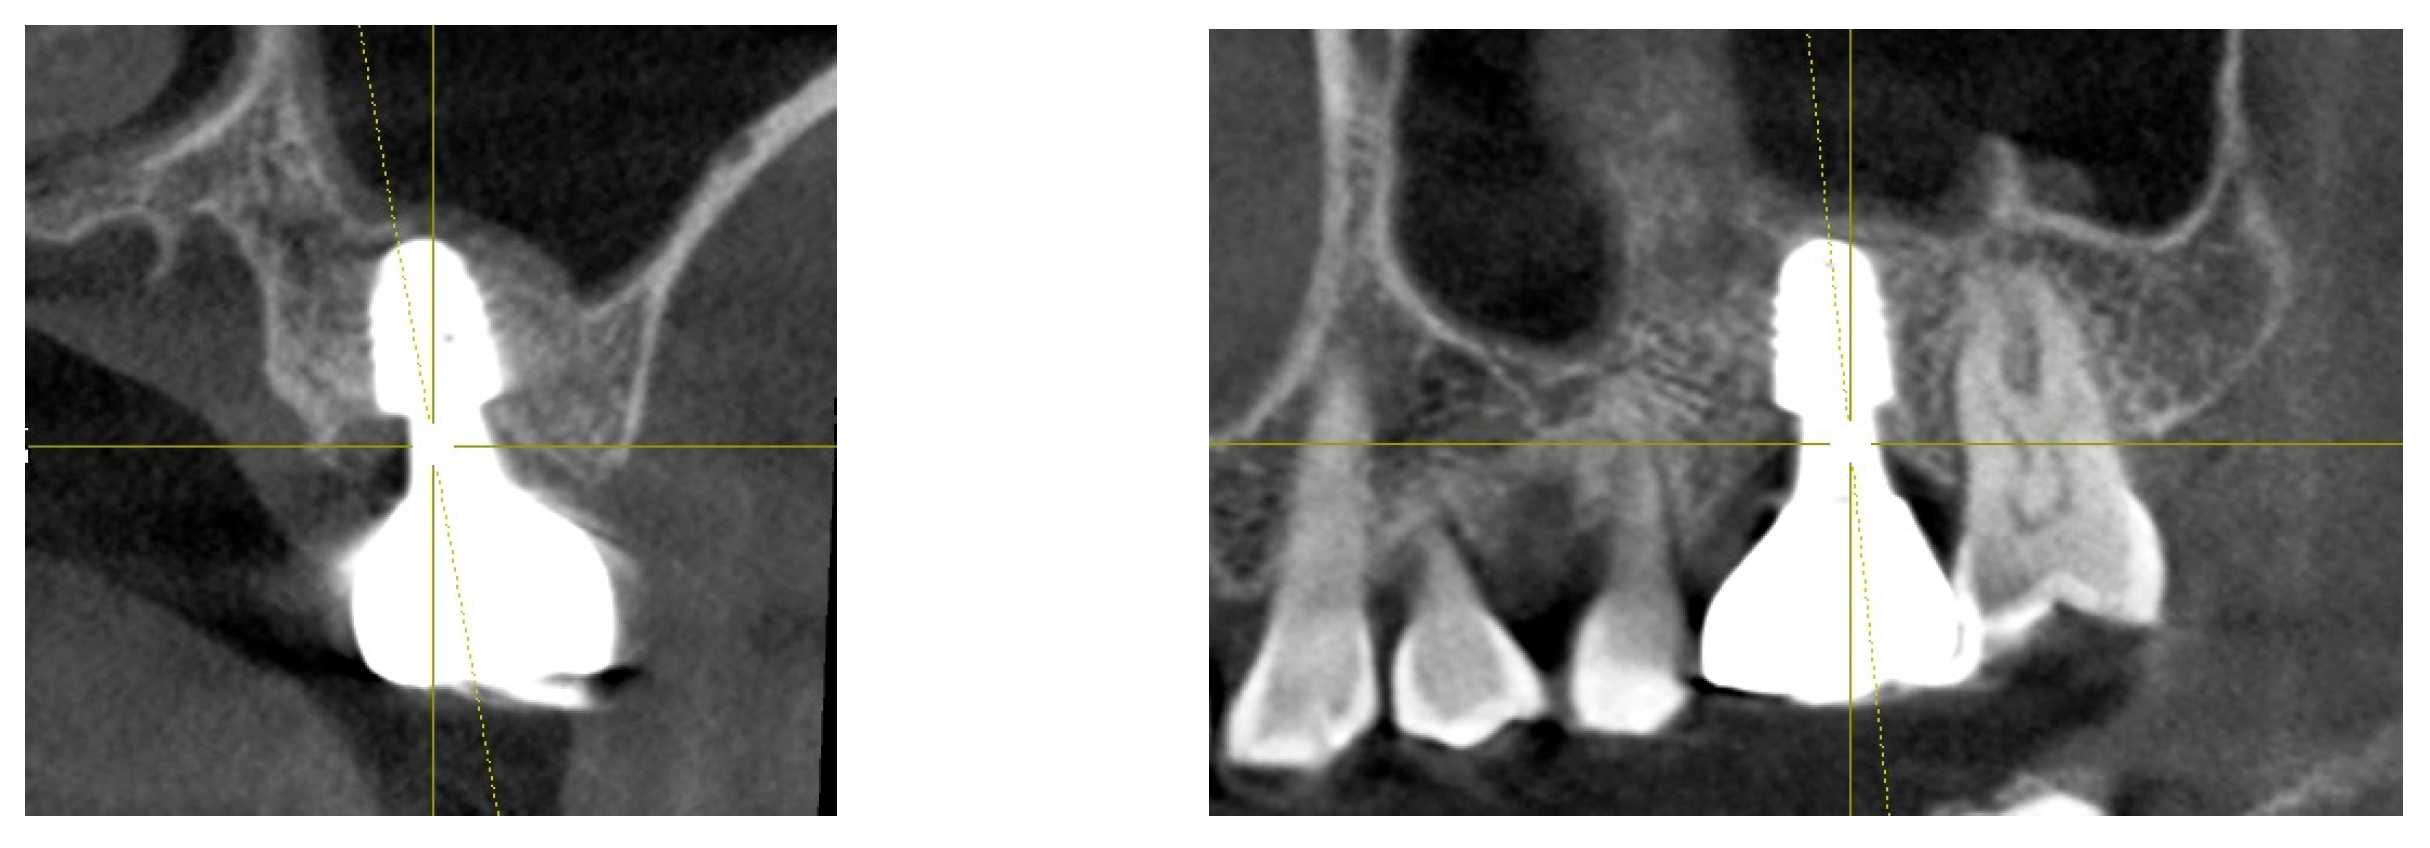

A 57-year-old woman underwent extraction of her lower right first molar on June 3, 2020, due to a severe periodontal abscess. Later, on September 22, 2020, her upper left first molar was extracted due to a fracture involving both the crown and root. (Figure 2)

Figure 2. Initial radiograph and clinical image of the upper left first molar on the patient’s first visit (September 22, 2020). The radiograph illustrates the condition of the tooth and surrounding structures. The clinical image provides a clear view of the crown and root fracture prior to extraction.